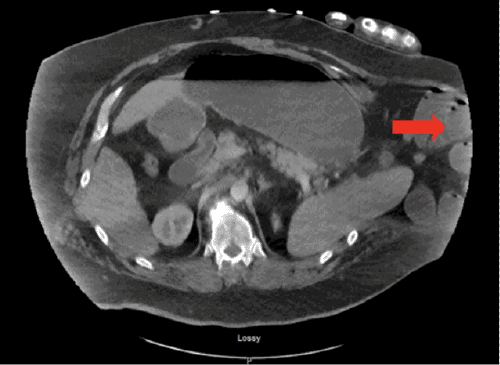

Initial empiric antibiotic coverage consisted of piperacillin-tazobactam and vancomycin, which was later tailored to daptomycin and micafungin based on culture results (details of specific organisms not provided here). A repeat CT scan of the chest at 48 hours showed near-complete resolution of the initial large pleural effusion, but a small, residual loculated fluid collection was noted just superior to the pulmonary hilum (Figure 5). This collection was deemed unsafe for percutaneous drainage by interventional radiology. Given its small size and the patient’s initial positive clinical response, a trial of non-operative management for this residual collection was pursued. Unfortunately, this collection progressed to a loculated empyema, ultimately requiring conversion from VATS to an open left thoracotomy due to dense adhesions and inadequate visualization. The empyema was evacuated, and a complete decortication of the left lung was performed (Figure 6). Following this definitive thoracic procedure, the patient recovered successfully and was eventually discharged to a skilled nursing facility after a total hospital stay of 28 days.

Figure 5. Follow-up CT Showing Residual Apical Pleural Collection. Published with Permission

Image demonstrates near-complete resolution of the large pleural effusion, with a small, residual loculated fluid collection (arrow) noted in the apex of the left lung, superior to the pulmonary hilum